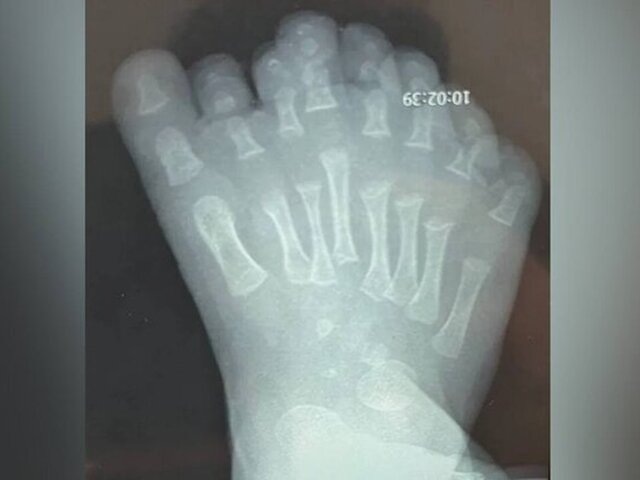

Иркутские врачи успешно прооперировали младенца с восемью пальцами на ноге

Специалисты Ивано-Матренинской детской клинической больницы в Иркутске оказали помощь семимесячному мальчику с полидактилией. Об этом сообщили в пресс-службе . С самого рождения ребенок имел восемь пальцев на правой ноге. Кроме того, у младенца было увеличено число плюсневых костей, что могло вызвать различные нарушения строения стопы. Изучив специфику кровоснабжения стопы пациента, медики приняли решение удалять сверхкомплектные фаланги и плюсневые кости, начиная со второго, а затем третьего и четвертого пальцев. Этот подход позволяет сохранить функциональность ноги и восстановить ее естественные размеры без чрезмерного повреждения тканей. В ходе хирургического вмешательства врачи успешно удалили мальчику лишние пальцы. Чтобы избежать формирования послеоперационного рубца, который мог появиться на эпидермисе, медики также были вынуждены выполнить кожную пластику. В пресс-службе больницы отметили, что к концу первого года жизни стопа ребенка должна полностью восстановиться, а кости – з

Фото: Ивано-Матренинская детская клиническая больница/

С самого рождения ребенок имел восемь пальцев на правой ноге. Кроме того, у младенца было увеличено число плюсневых костей, что могло вызвать различные нарушения строения стопы.

Изучив специфику кровоснабжения стопы пациента, медики приняли решение удалять сверхкомплектные фаланги и плюсневые кости, начиная со второго, а затем третьего и четвертого пальцев. Этот подход позволяет сохранить функциональность ноги и восстановить ее естественные размеры без чрезмерного повреждения тканей.

В ходе хирургического вмешательства врачи успешно удалили мальчику лишние пальцы. Чтобы избежать формирования послеоперационного рубца, который мог появиться на эпидермисе, медики также были вынуждены выполнить кожную пластику.

В пресс-службе больницы отметили, что к концу первого года жизни стопа ребенка должна полностью восстановиться, а кости – занять правильное положение.